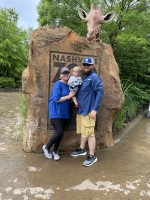

I am McKenzie Baxter a 24 year old wife, mama, and cancer survivor. November 25, 2023 I received the news I had Acute Myeloid Leukemia. I was 23 years old at the time and just had my first son in January of 2023. My journey of gaining the diagnosis took time. I am a type one diabetic as well as this is important to remember. June of 2023 I had just a fatigue I could not shake. My son had slept through the night since he was two months old so I felt there was not really a reason for me to be as tired as I was feeling. I also started getting random bruises very easily. I had thought maybe diabetic related or my thyroid was not acting right. I scheduled an appointment with my primary care provider and we did blood checks and also checked the function of my thyroid. My thyroid looked great, but my white blood count, red blood count, platelet levels, hemocrit, and hemoglobin levels were very low. I ended up needing a blood transfusion and a referral to hematology/oncology.

We had been traveling to see family and once we got home I shaved my head. I knew mentally it would be so much harder on me to sit and watch my hair fall out. My husband had helped me and it was very emotional for the both of us. My Husband and I have been dating since 2015 and married since 2020. He has been my rock through so many things. That Monday I chose to go to work and so afterwards I went to pick our son up who was ten months old at the time from daycare. As I pulled in to pick him up I received a call from Sarah Cannon Cancer Center stating I would be admitted from 4-6 weeks the next day to start treatment. I felt broken. I was breastfeeding my son and so this had to come to a stop. I felt as if I was being took away from being a mother. Growing up I had always wanted to be a mom and every part of me enjoyed being a mom more than anything.

During the first hospital stay I struggled with being away from my husband, son, and our dogs. I had missed my sons first Christmas which as a first time mom, and Christian this was hard for me. Thankfully he spent Christmas with my sister, nieces, and nephews who love him unconditionally. My husband had spent Christmas with me. We just felt this is what we both needed and to ensure our son had a great Christmas. During my hospital stays my mother would stay during the week with me and then on weekends my husband would come, my dad, or my sister. My husband stayed home and worked and also became Mr. Mom as we jokingly say. As a cancer patient children under the age of typically fifteen are not allowed on the cancer floors due to risk of spreading illnesses to those who are immune compromised. I spent 4 weeks before I got to see my son. This was the hardest part of treatment. He did not know who I was for a solid thirty minutes. As a mom you can understand how much this broke me. I spent a total of 6 weeks in the hospital during my first stay. I finally had a breakdown and just absolutely needed to go home. I do work in the healthcare so I understand precautions to take and how to be safe at home.

The chemotherapy treatments I responded the first round and went into remission but it came back and I had to do two other consolidation rounds. The side effects from chemotherapy typically would be decreased appetite, fatigue, nausea, vomiting, very sensitive skin, bone pain, hair loss, and changes in skin coloration. The end of March I started my ablative chemotherapy in preparation for my bone marrow transplant. I had my bone marrow transplant April 5 of 2024. My doctors chose the route of using a donor due to my family medical history. I was lucky to have multiple matches and so the doctors narrowed down the list and figured out who would be the best candidate for me. I have been in complete remission since and have done wonderful. The week of and after my transplant I was very tired and weak. Eventually my energy started coming back and so did my strength. Now I am currently in Nursing school. I also already have my surgical technology and certified surgical first assistant. I figured since being out of work now would be a good time to go to school and just further my education.